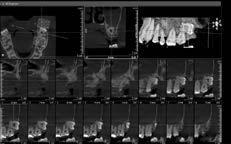

Prótese Protocolo Digital: O uso da Sequência de Fibonacci em implante dentário

52 Cirurgia do Terceiro Molar: O que precisa saber